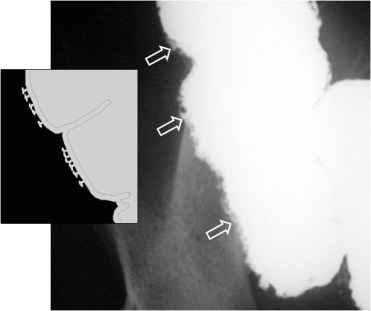

Úlcera de la mucosa que se extiende a la submucosa del colon, de cuello estrecho y profundo y base ancha (en forma de «T» o»botón de camisa») que se ve en la colitis ulcerosa, la enfermedad de Crohn, amebiasis, etc.

En algunas zonas, las úlceras se unen formando un carril paralelo a la pared del colon, como se muestra en el esquema. En la imagen, un paciente con colitis ulcerosa.